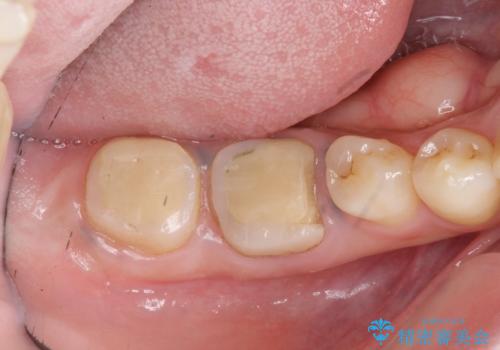

治療途中で長期間放置していたため、歯が歯ぐきから挺出(伸びてくる)してしまい、十分に強度を担保できるセラミッククラウンを装着するスペースが不足した状態です。

加えて、舌の邪魔になっている骨隆起や根尖病変といった問題を歯周外科・精密根管治療を行い、しっかりとスペースを確保したのちセラミッククラウンを作製していきます。

- 37.4万円(ジルコニアクラウン×2・仮歯×2・歯周外科手術)費用は治療当時の料金となります